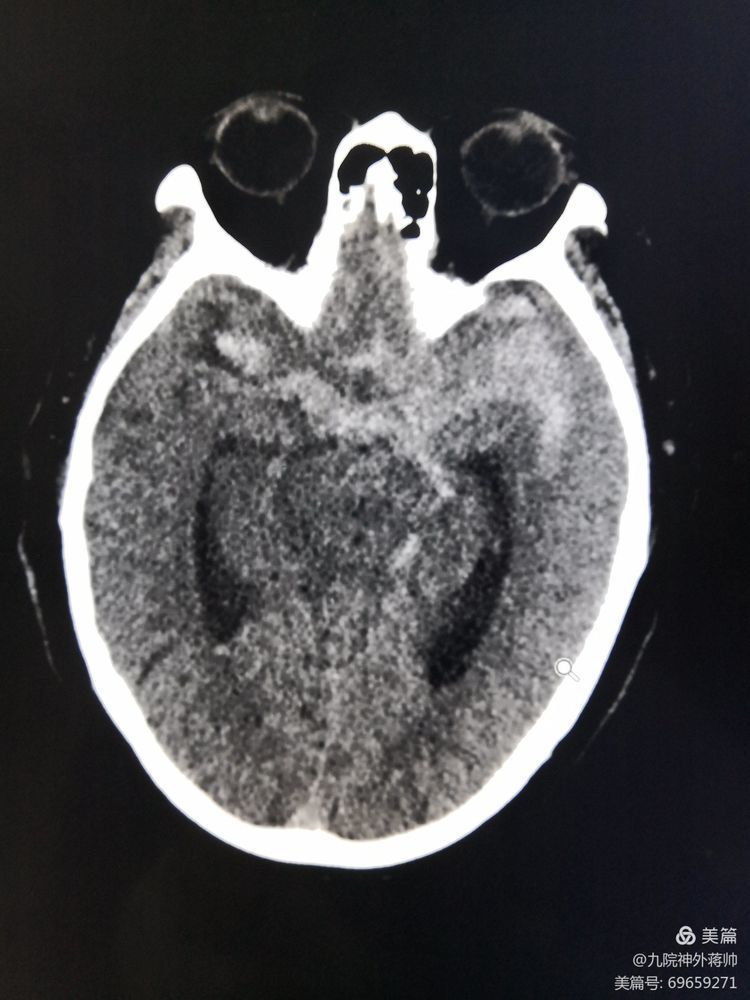

10月4日深夜, 85岁高龄的徐老师来九院就诊。来院4小时前,徐老师还和往常一样做着家务,突然出现剧烈头痛,伴随频繁呕吐,逐渐出现意识不清。急诊送到我院后进行颅脑CT检查提示,检查提示:蛛网膜下腔出血。

询问患者老伴后得知徐老师既往有高血压多年,医生结合颅脑CT结果,高度怀疑患者颅内动脉瘤破裂。刘展会主任急诊为徐老师行全脑血管造影术,术中证实患者存在十分复杂的颅内动脉瘤,动脉瘤位于左侧大脑中动脑的分支,同时发现动脉瘤呈宽颈,存在子瘤,并且累及大脑中动脑分支上干。